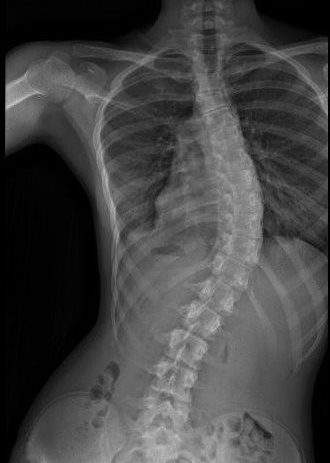

junio 30, 2025 – Diagnosticada con escoliosis a los seis años, Naomi ha estado luchando duro para evitar que su columna vertebral se curve aún más. Después de años de probar varias opciones de tratamiento, y con la pubertad causando una mayor progresión de la curva, Naomi y su familia buscaron otras opciones de tratamiento. Fue en Nicklaus Children’s Instituto de Ortopedia, Medicina Deportiva y la Columna Vertebral donde Naomi y su familia encontraron consuelo y esperanza.

Natalie fue diagnosticada con escoliosis de inicio temprano a los 19 meses y se sometió a años de tratamiento, que incluyeron yesos, aparatos ortopédicos y tres cirugías, bajo el cuidado del Dr. Stephen G. George. A los 12 años, después de su última cirugía para corregir su columna vertebral, completó su jornada de tratamiento de 10 años y está lista para seguir adelante.